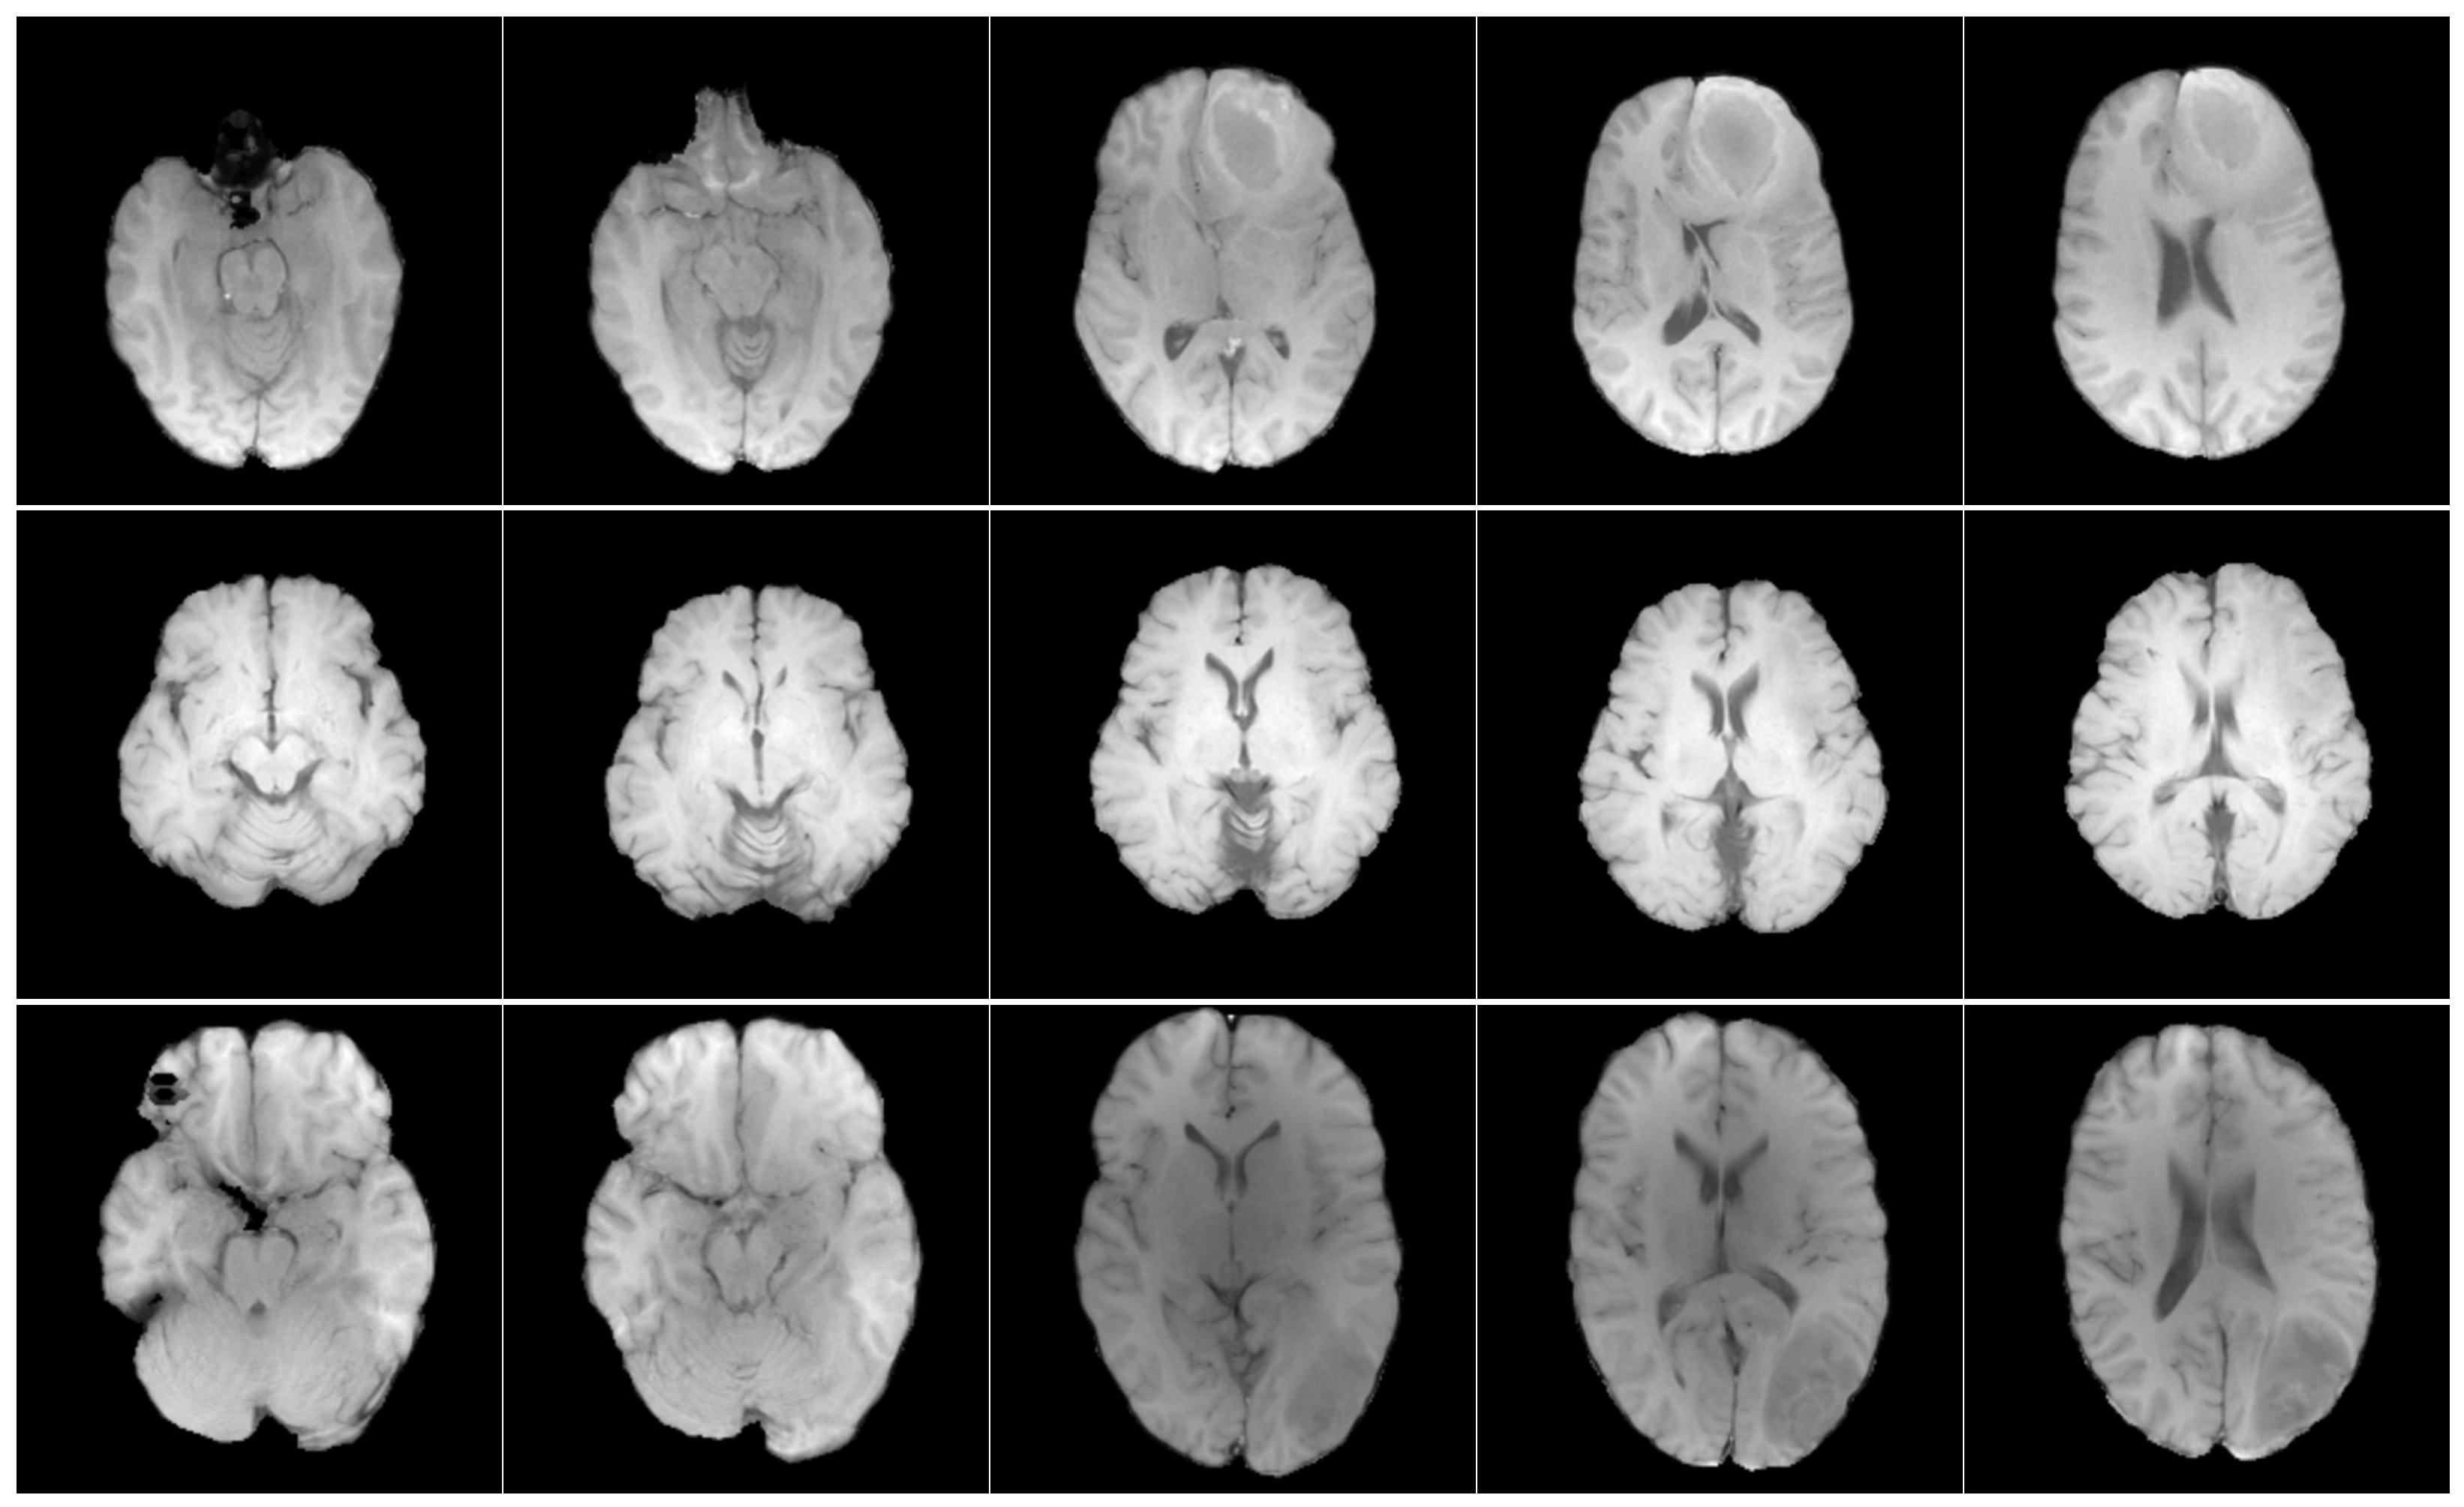

The RSNA and MICCAI developed a data set named the RSNA-MICCAI brain tumour radiogenomic classification for the BraTS 2021 challenge [21], which is available to the public through the Kaggle platform. This data set comprises multi-parametric magnetic resonance imaging (mpMRI) scans acquired from multi-institutional benchmarks, retrospectively collected for the prediction of a specific genetic characteristic of GBM, namely, the MGMT promoter methylation status, fulfilling strict inclusion criteria for image quality and diagnostic confirmation. An mpMRI scan typically includes four imaging modalities, each contributing distinct contrast mechanisms that facilitate tumour characterisation. In this study, only T1w images were selected for analysis (Figure 1), as this sequence provides the most morphologically informative signal [27]. All images were standardised to a resolution of 512 × 512 pixels to guarantee uniformity between analyses.

Figure 1. Axial T1w pre-contrast MRI slices from the RSNA-MICCAI data set. Each row shows a different patient, and each column shows a different slice from the same scan.